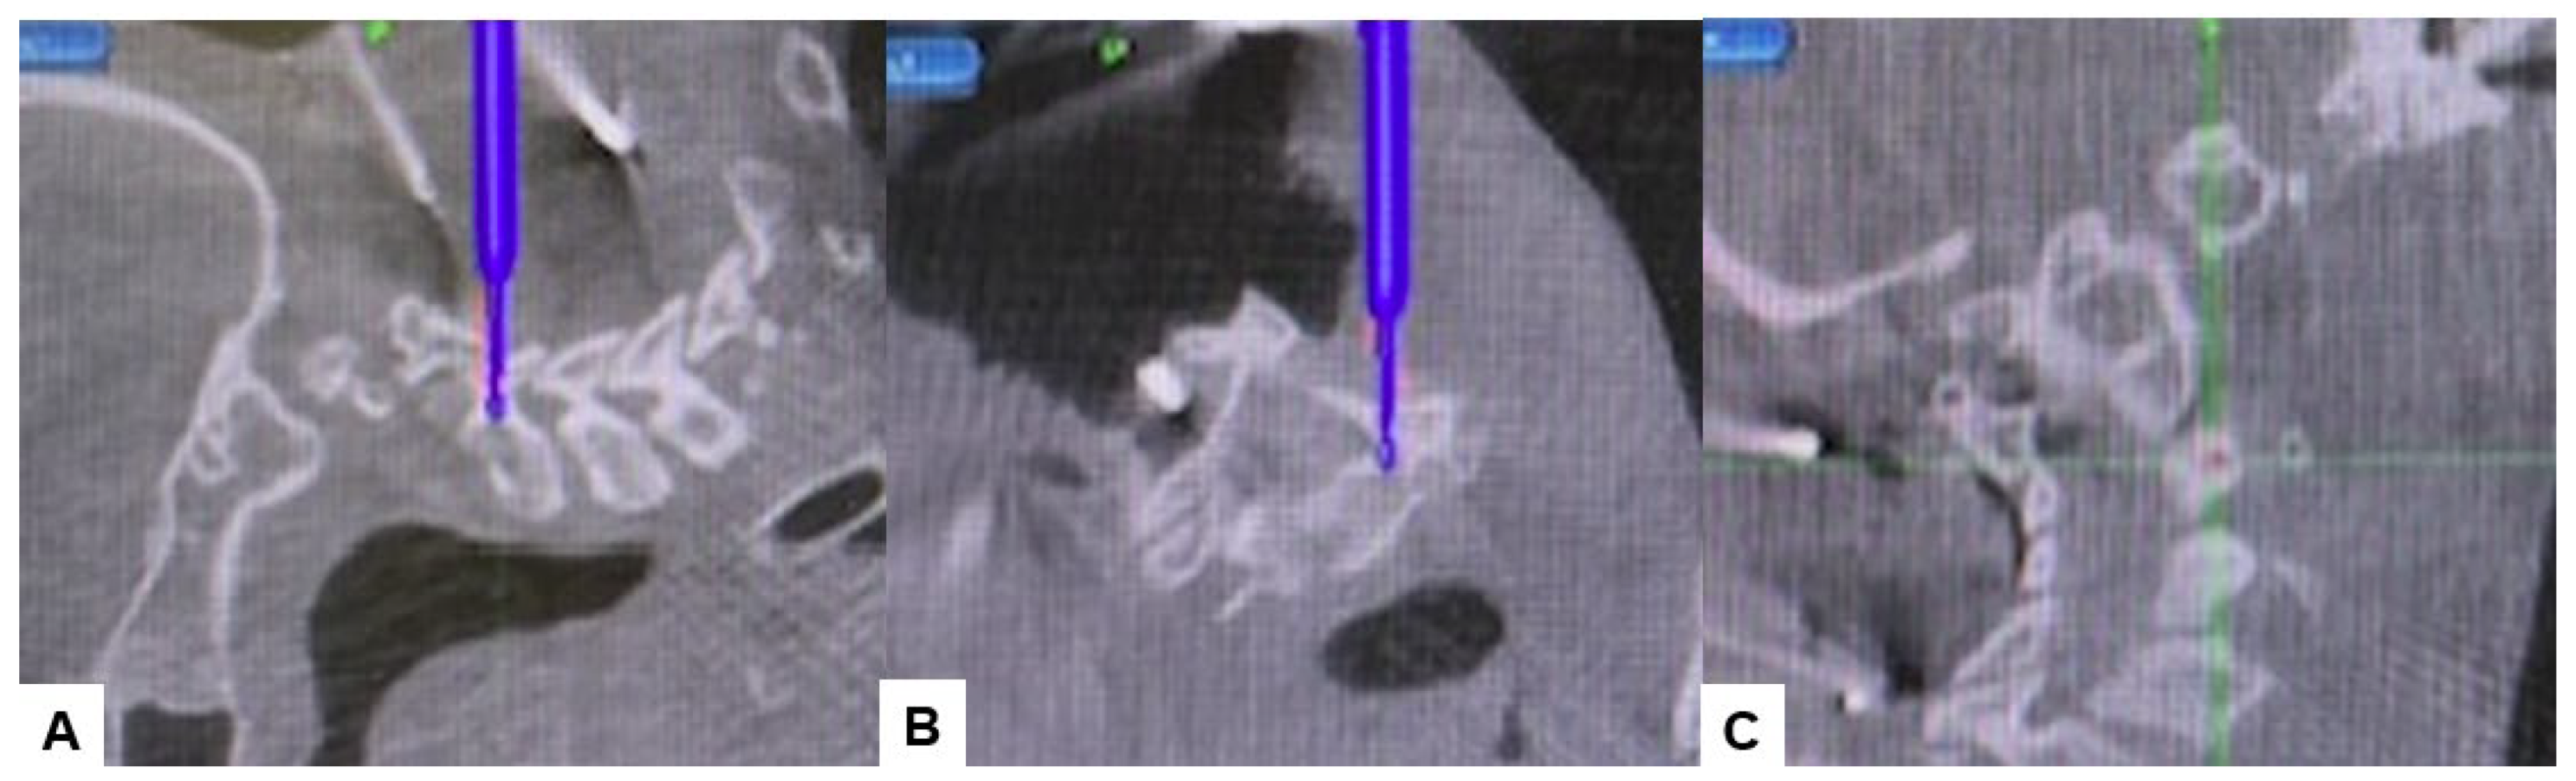

Subsequently, the O-arm was positioned, and three-dimensional (3-D) reconstruction images were obtained. Following the verification of each navigated mapped spinal instrument, bilateral C2 laminar screws (Figure 7) and C4–5 pedicle screws (Figure 8) were inserted under navigation. Pedicle screws were not inserted into the C2 vertebra because of bony anomaly and vertebral arteries course.

Figure 7.

Bilateral C2 laminar screw, (A) sagittal view, (B) Axial view, (C) Oblique view.

Figure 8.

Pedicle screw fixation, (A) sagittal view, (B) Axial view, (C) Oblique view.